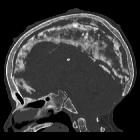

developmental and genetic origin affecting the paediatric craniofacial skeleton. Typical manifestations of nevoid basal cell carcinoma syndrome (NBCCS) in a 16-year-old boy. a Orthopantomography (OPT) shows cystic lesions of the mandible and maxilla (arrows), with unilocular and multilocular pattern and smooth or scalloped borders associated with displaced and unerupted permanent teeth. b Coronal CT scan (bone window) shows ectopic calcifications of the falx cerebri and tentorium cerebelli (arrows) and spotted meningeal calcifications (arrowheads). Brain MRI reveals a cavum veli interpositi on axial T2 (asterisk in c) and coronal contrast-enhanced T1 (asterisk in d) and also vermian dysgenesis (arrowheads in d)